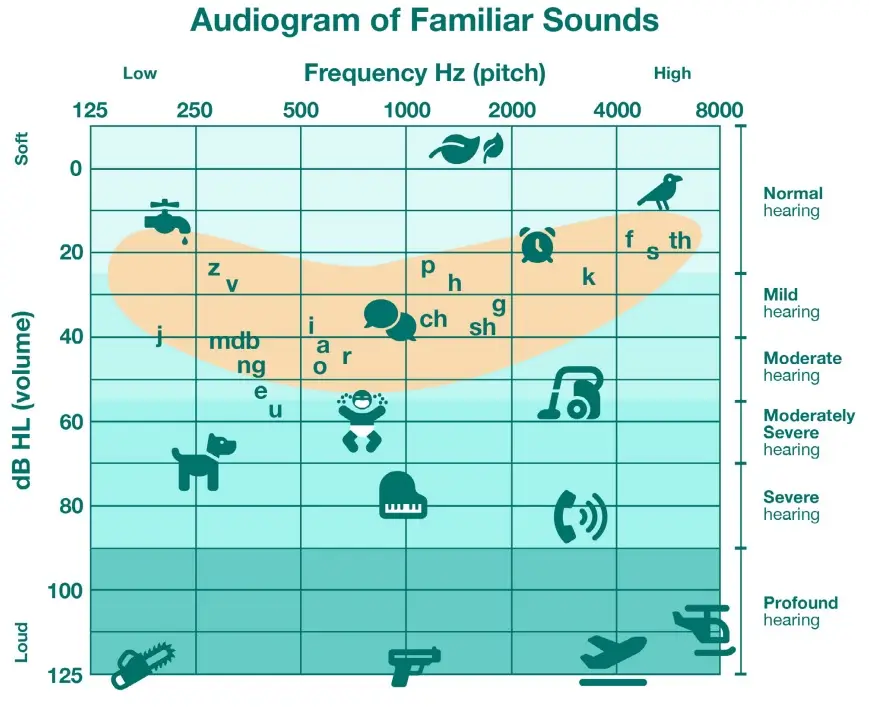

Hearing loss occurs when a person cannot hear as well as someone with normal hearing, defined as hearing thresholds of within 15 dB or better in both ears. It can range from mild to profound, affecting one or both ears and may lead to challenges in understanding conversational speech or hearing loud sounds